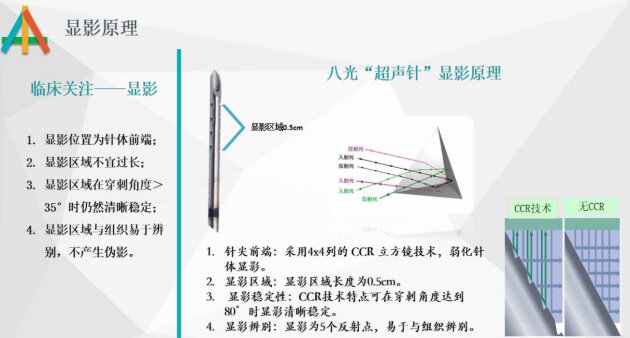

✅ “超声下神经阻滞针”的天花板 <日本.八光>

0.5cm精准显影,80°穿刺角度仍清晰稳定,无伪影易辨别,让临床穿刺更精准、更安全。